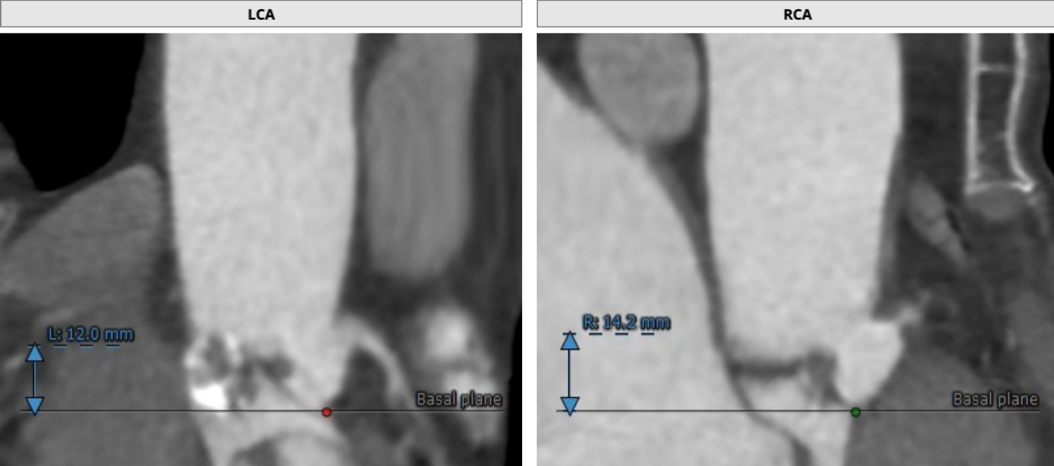

患者为73岁老年男性。CT评估显示其为三叶瓣,伴有轻度钙化,双冠高度可,升主动脉未见明显增宽,主动脉弓部角度平缓。瓣环最短径为17.6mm,最长径为24.7mm,平均瓣环直径为21.1mm。升主动脉平均直径33.6mm。左冠开口高度12.0mm,右冠开口高度14.2mm,冠脉阻塞风险低。外周血管未见明显钙化,最窄处直径为5.7mm。入路情况较佳。

冠脉开口高度可,未有瓣叶遮挡征象